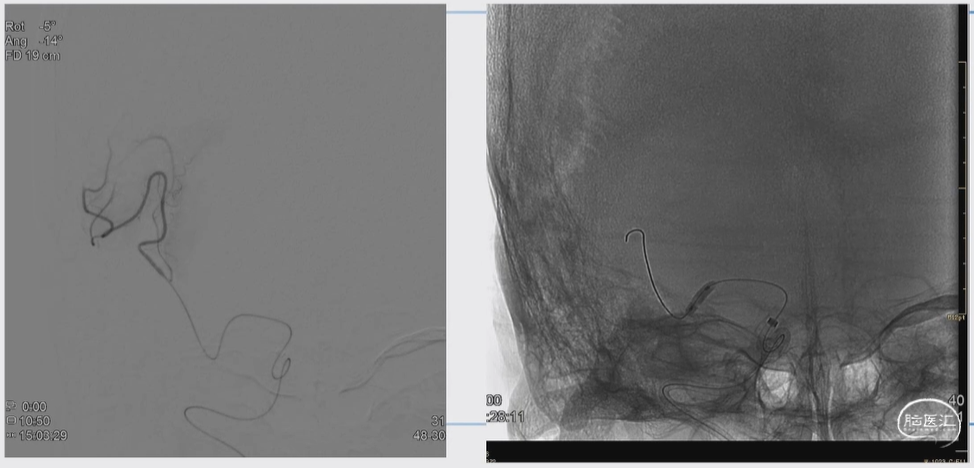

图片示例

第一次取栓时

上图与本手术无关,但提示双抗+他汀类药物的神奇疗效

左侧为第一次取栓术后的图片,当时放了Solitaire支架,血管很差。

右侧为取栓术后四个月复查的图片,血管恢复良好形态

说明:对于硬化性狭窄,双抗加上他汀类药物有神奇的疗效